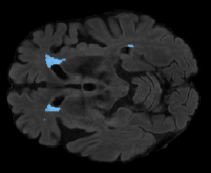

FLAIR

[Uncaptioned image] [Uncaptioned image] [Uncaptioned image]

T1

Ground Truth

Unimodal

Offline synthesis

Proposal

Table 2: Segmentation results for all proposed methods, each column represent a different slide in the image, blue areas are regions which were correctly labeled, false positives are shown in green, and false negatives in yellow

In order to better understand the above results, we visually analyzed the output segmentation performed for each method. Table 2 shows the results for three different slices (one slice per column). As illustrated, the proposed method is able to produce less false positives. It is also important to note that, unimodal segmentation is the one that produces more false positives, showing the advantage of using synthetic data. Regarding the nature of false positives, it can be easy to see in the third column a large number of false positives are on the border of periventricular lesions for the Unimodal method in comparison to the proposed method. Also from the first and second column, it can be observed that Unimodal tend to produce more small regions of false positives near to cortical areas. Removing such false positives requires additional post-processing steps, therefore, it is of value avoid this kind of over-segmentation. It can also be noted that synthesis methods tend to produce the same kind of false negatives, this may be due to the blurring effects in synthesized images since the information available during testing is limited – which otherwise is available from a FLAIR sequence.